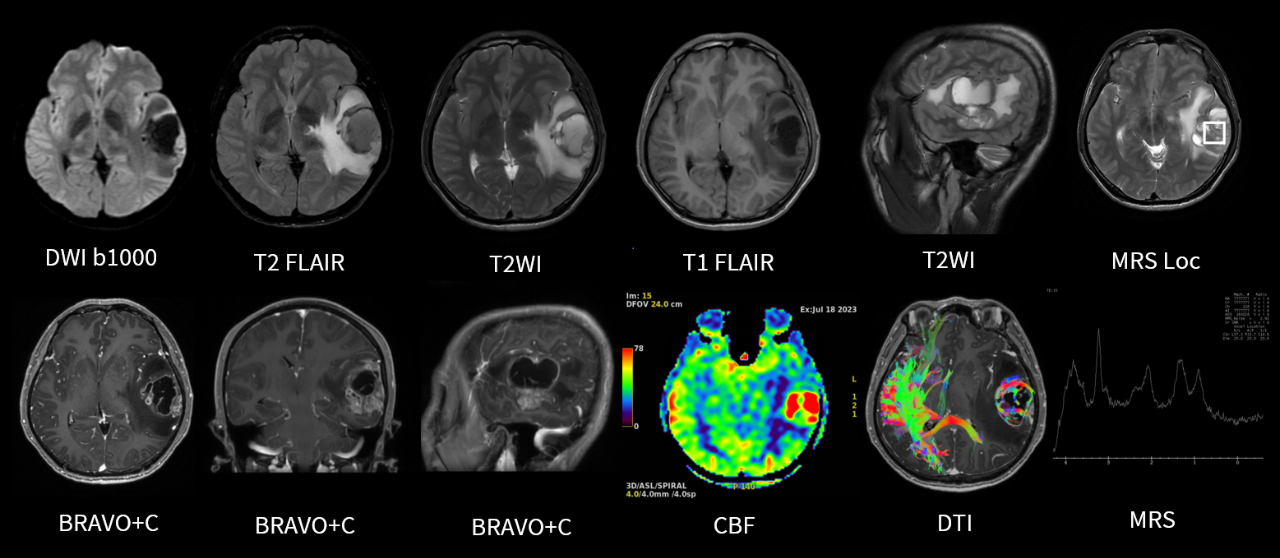

★图像质量高清!实现精准临床科研成像,高清的图像质量,可实现微小病灶的精细显示与分析,让病灶无处遁形,尤其在肿瘤和损伤的诊断方面独具优势。

★应用范围更广!能够完成包括神经系统、胸部、腹部、盆腔、心血管、骨骼关节、软组织、乳腺等全身各部位磁共振检查。